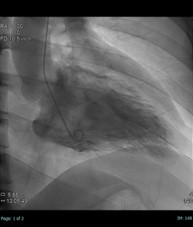

手や足の血管からカテーテル(血管より細く長い管)を挿入し、造影剤1)を使用しながら連続的にX線撮影して、心臓や冠状動脈(心臓に栄養を送る血管)の造影を行います。

③心臓(主に冠動脈3))の撮影を行います。